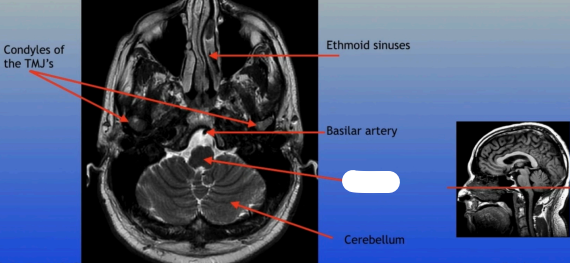

Condyles of the TMJ

Ethmoid Sinuses

Basilar Artery

Cerebellum